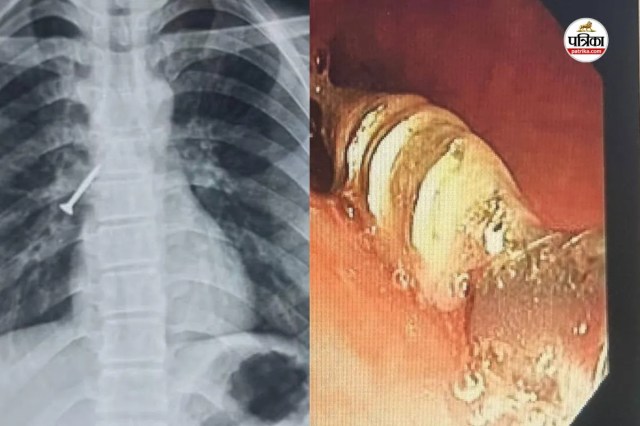

उदयपुर। आरएनटी मेडिकल कॉलेज अधीन संचालित संभाग के सबसे बड़े टीबी एवं चेस्ट अस्पताल, बड़ी के चिकित्सकों ने जटिल और जोखिम भरे मामले में 17 वर्षीय युवक की श्वास नली से 32×4 मिमी का लोहे का स्क्रू निकालकर उसे नया जीवन दिया।

यह प्रोसिजर बिना चीर-फाड़ और बिना जनरल एनेस्थीसिया के संपन्न किया। मरीज को शनिवार को अस्पताल में भर्ती किया था। स्थिति की गंभीरता देखते हुए चिकित्सकों ने तुरंत जांच कर रविवार को ‘फ्लेक्सिबल ब्रान्कोस्कोपी’ तकनीक से सफल प्रक्रिया को अंजाम दिया।

सहायक प्रोफेसर डॉ. महेश माहिच ने बताया कि युवक सुथारी का काम करते समय गलती से लंबा स्क्रू निगल गया, जो दाहिने फेफड़े की श्वास नली में फंस गया। इससे मरीज को तेज खांसी, छाती में दर्द और बलगम में खून आने जैसी गंभीर समस्याएं होने लगीं। समय रहते उपचार न मिलने पर स्थिति जानलेवा भी हो सकती थी।

सीनियर प्रोफेसर डॉ. महेन्द्र कुमार बैनाड़ा के मार्गदर्शन में टीम ने जटिल प्रक्रिया सफलतापूर्वक पूरी की। विशेषज्ञों के अनुसार, सामान्यतः ऐसे मामलों में मरीज को बेहोश कर सर्जरी या रिजिड ब्रान्कोस्कोपी की जरूरत होती है, पर टीम ने अत्याधुनिक ‘फ्लेक्सिबल ब्रान्कोस्कोपी’ का उपयोग कर न्यूनतम जोखिम में ही फंसी वस्तु को बाहर निकाल लिया।